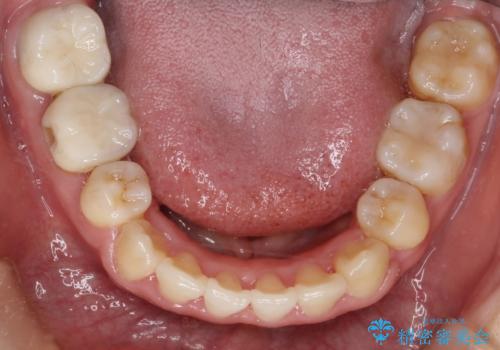

上下の歯のガタガタ ワイヤーでの抜歯矯正で整った歯並びへ

- 上下の歯のガタガタを治したいとのことで来院されました。

がたつきの度合いが強いのと、口元をなるべく引っ込めたい希望がありましたので、ワイヤーでの抜歯矯正となりました。

ガタガタが重度の方は抜歯が必要となることが多いです。

抜歯スペースを使って前歯を引っ込めることにより、口元の突出感も改善できました。